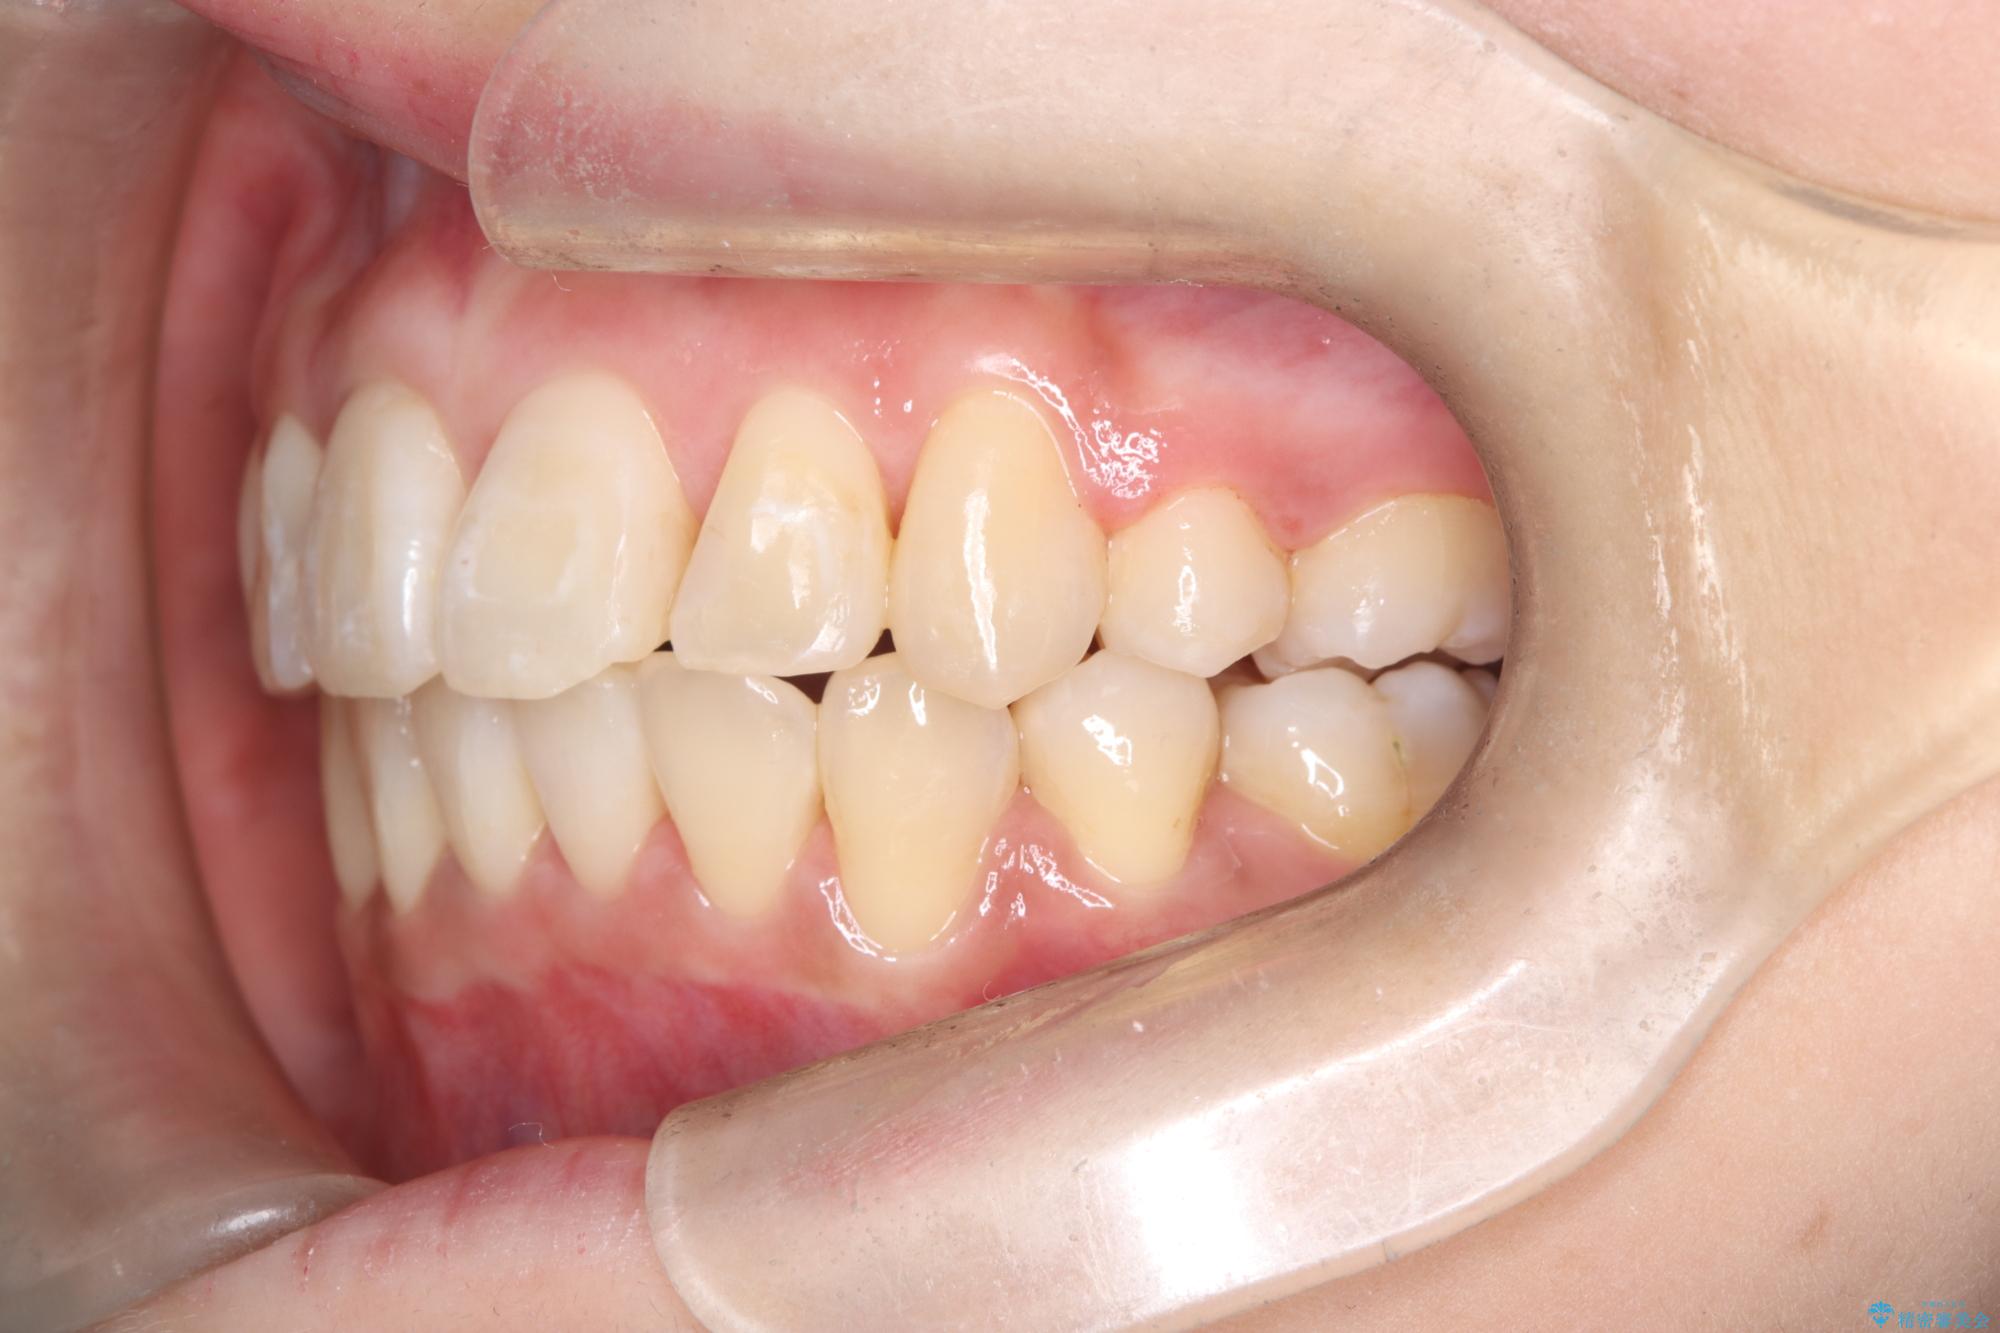

正中のズレ: 歯を左右対称に移動させることで、上下の歯の中心線を正確に合わせ、顔全体のバランスも改善しました。

治療の結果、長年気にされていた八重歯と正中のズレが解消し、機能的にも整った理想的な歯並びを獲得。目立たない装置で治療を完遂し、自信を持って笑える美しい笑顔を手に入れていただけました。